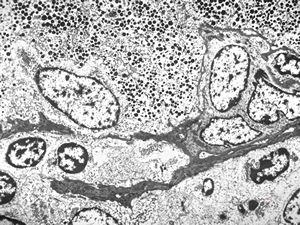

F, 45y. | carcinoid … liver metastasis